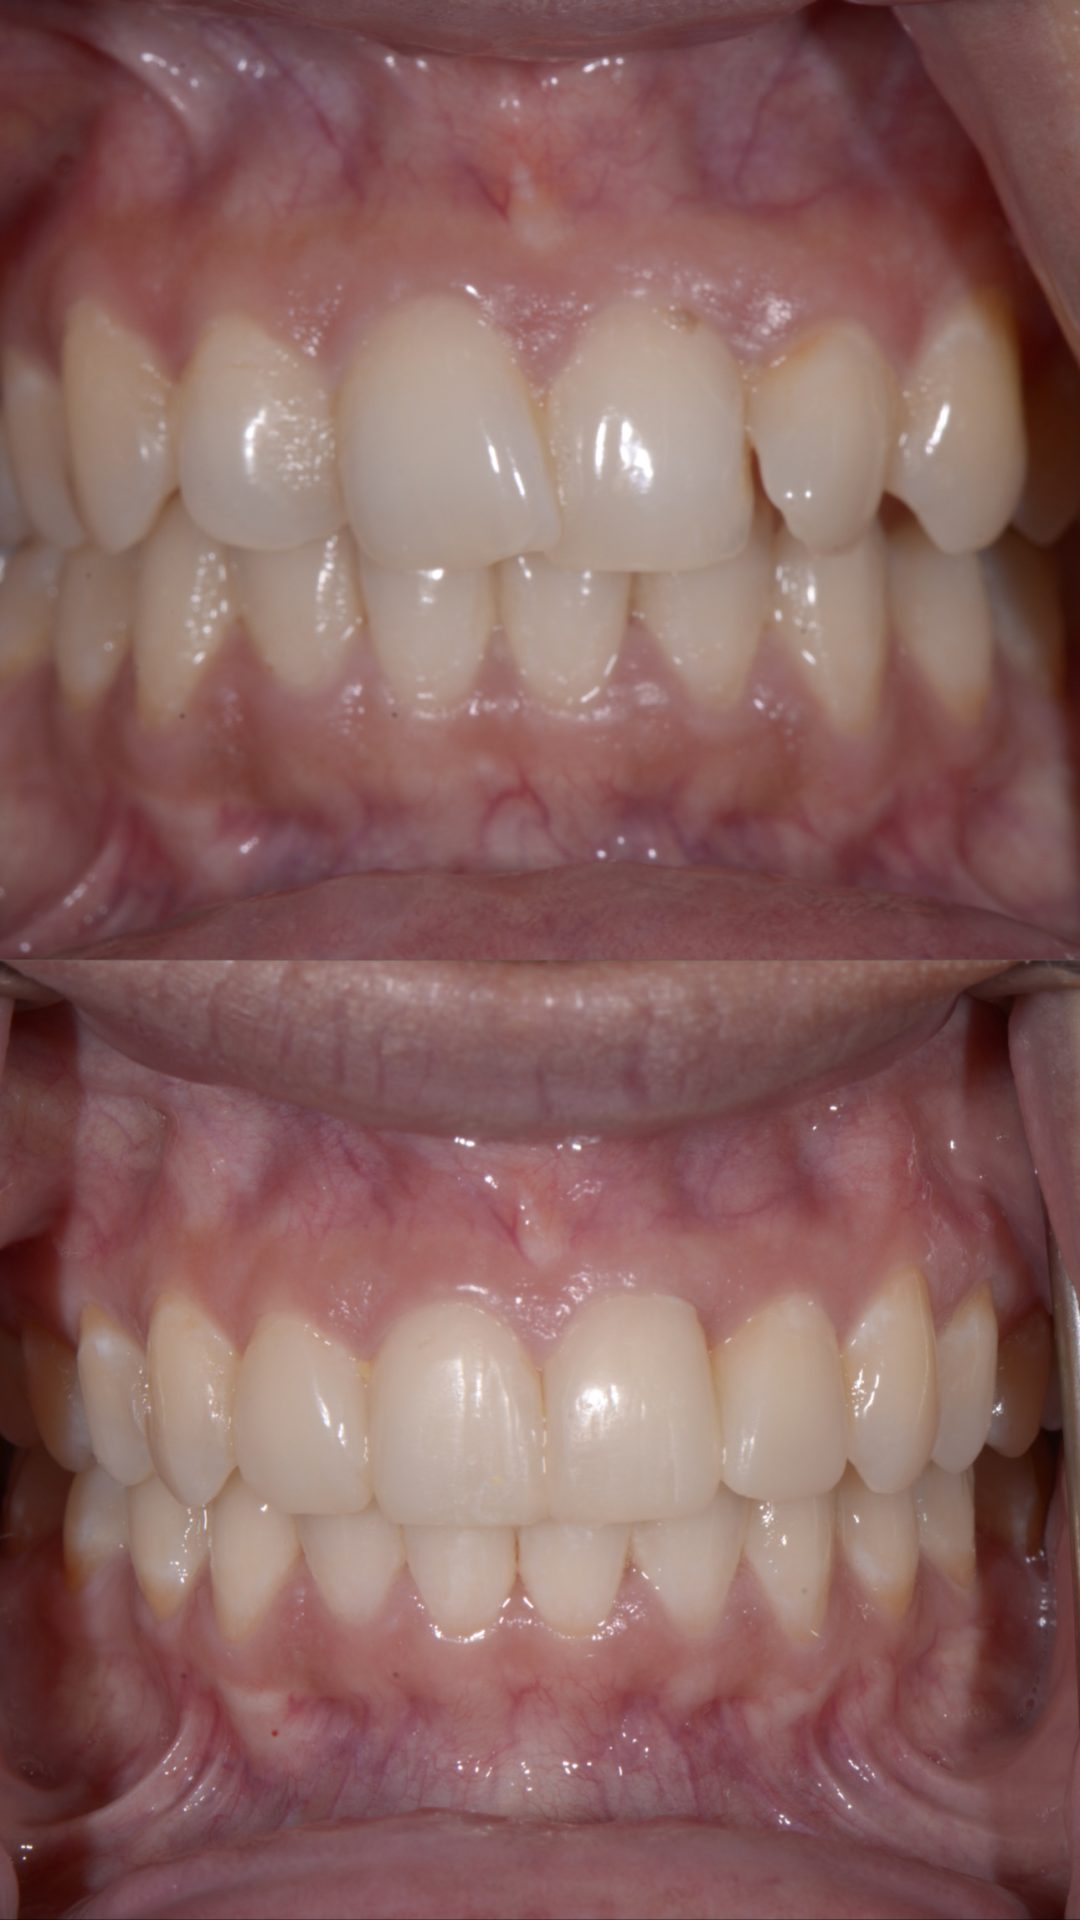

Orthodontic Makeovers